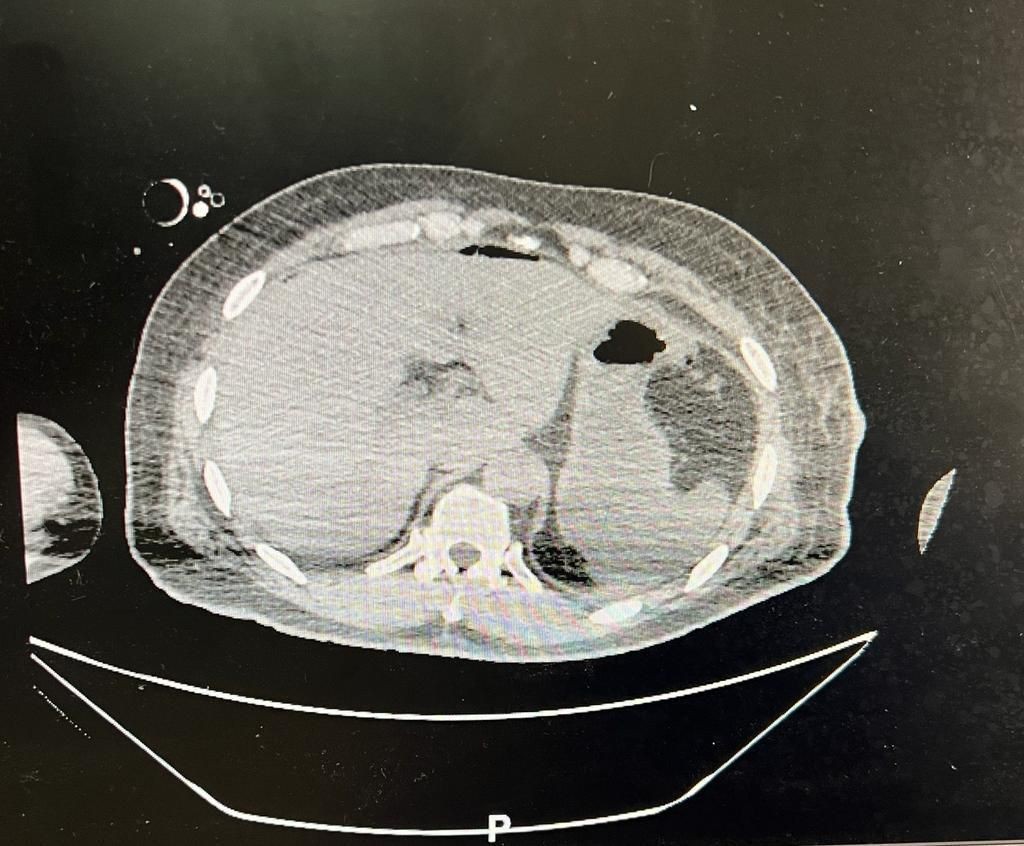

وأوضح استشاري الجراحة العامة الدكتور محمد مرزا أن المصاب حضر الى قسم الطوارئ والحوادث في حالة حرجة وهو يعاني من اصابة  إثر تعرضه لطعنات بآلة حادة مع هبوط حاد في ضغط الدم، وعلى الفور تم نقله الى غرفة العمليات كحالة إنقاذ حياة وأجريت له عملية استكشافية للبطن بمشاركة قسم التخدير وأتضح وجود قطع في عضلة الكتف ونزيف داخلي ونزيف شديد في الطحال  والبنكرياس والاثنا عشر مع إصابة في القفص الصدري.

وأجري للمريض عملية استئصال للطحال وخياطة العضلات والجلد للكتف والسيطرة على النزيف الدموي في التجويف البطني والصدر وإيقاف نزيف البنكرياس  والاثنا عشر.